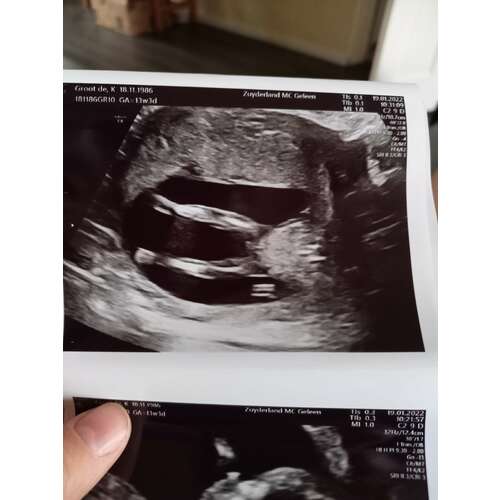

Wat denken jullie? Hier is mijn vrouw 12+4

Niet zo goed te zien had je nog een foto?

Dit is de andere